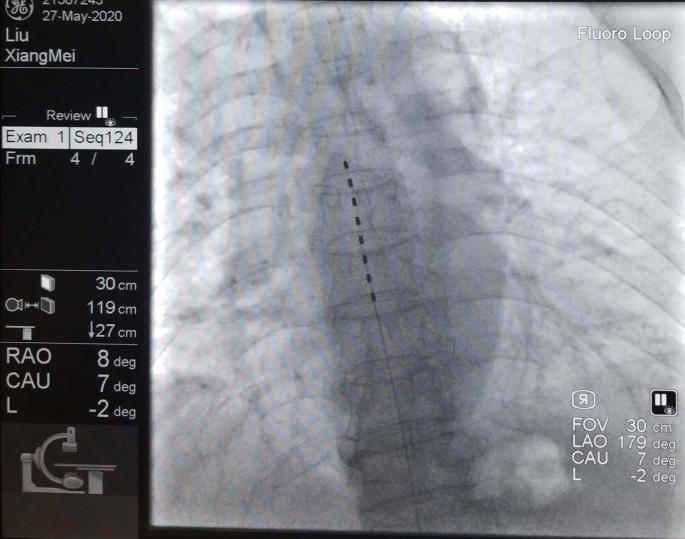

二、影像引導下脈沖射頻技術治療慢性神經性疼痛、手術后疼痛綜合癥、神經卡壓綜合癥等。

三、椎間盤微創介入技術,如:等離子消融、射頻熱凝術、臭氧髓核溶解術治療頸腰椎間盤突出癥、椎間盤盤源性疼痛。

四、經皮微球囊壓迫技術與三叉神經半月節射頻熱凝術治療三叉神經痛。

五、脊柱椎間孔鏡技術治療腰椎間盤突出癥。

八、脊髓電刺激植入術治療帶狀皰疹后神經痛與頑固性疼痛。